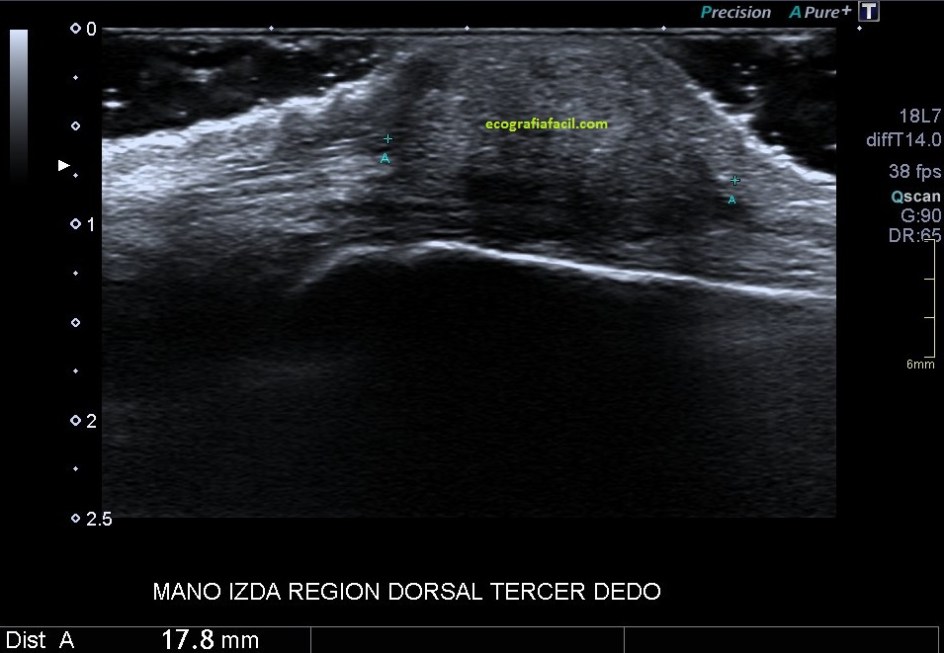

Se explora ecográficamente con sonda de alta resolución la región dorsal del tercer dedo de la mano izquierda, a la altura de la articulación metacarpofalángica.

Coincidiendo con el área palpable se identifica una lesión sólida de 13,8 x 9,6 x 17,8 mm, de aspecto heterogéneo, predominantemente hipoecogénica, aunque con áreas más hiperecogénicas en su interior, que predominantemente se encuentra superficial con respecto al tendón extensor del tercer dedo y con discreta vascularización periférica en el estudio Doppler color.